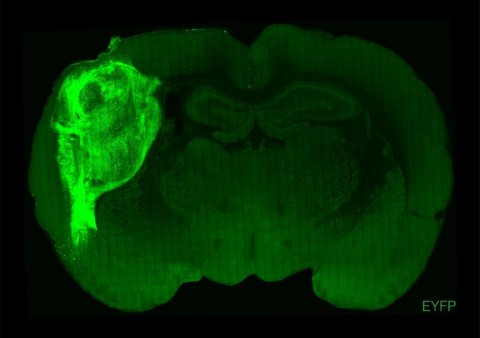

To overcome those limitations, researchers implanted the groupings of human brain cells, called organoids, into the brains of young rats.

"By transplanting them at these early stages, we found that these organoids can grow relatively large, they become vascularised (receive nutrients) by the rat, and they can cover about a third of a rat's (brain) hemisphere," Pasca said.